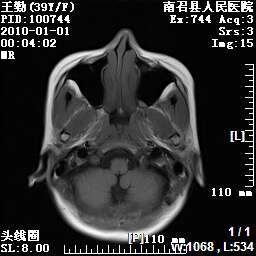

以下是引用随光逐影在2010-1-22 9:03:00的发言:[br]考虑左侧中颅窝(蝶骨翼区)脑膜瘤侵犯蝶骨翼并突入左侧眼眶。

以下是引用水过无痕在2010-1-22 14:55:00的发言:[br]一、定位:颅外占位;二、定性:恶性可能性大;三、组织来源:来源于左侧眼外直肌或其他部位;考虑为:横纹肌肉瘤>转移瘤>脑膜瘤.